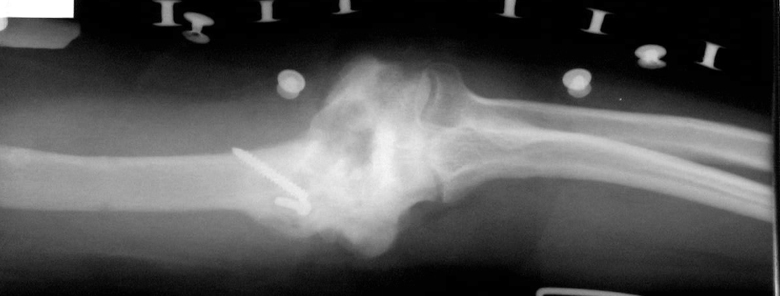

Psödartroz tedavisinde alt ekstremitede kaynama elde edilmesinin yanında kemik boylarının da eşitlenmesi amaçlanır. Buna karşın humerus diafiz psödartrozlarının tedavisinde 4-5 cm’ ye kadar olan ekstremite uzunluk farkları kabul edilebilir sınırlardadır; fonksiyonel ve kozmetik yönlerden morbidite oluşturmaz. Ring ve ark. defektleri kortikospongiöz otogreft ve dinamik kompresyon plağı ile köprülemişlerdir. Buna karşın defekt rekonstruksiyonunun hastaların fonksiyonlarına istatistiksel açıdan anlamlı bir etkisi olduğuna değinmemişlerdir.Ortalama 2.4 (1-5) cm tespit edilen kısalığın fonksiyonlarını ve kozmetik görünümlerini etkilemediği görüldü. Bu nedenle 5 cm’ ye kadar olan defektlerde monofokal girişim yapılmasının hem tedavi süresini hem de sonucunu olumlu yönde etkileyeceğini düşünmekteyiz. Buna karşın 6 cm ve üzerindeki defektlerde bifokal kompresyon distraksiyon uygulaması ile humerus uzunluğunun da restorasyonu sağlanabilir. Gür ve ark. humerus psödartroz tanısı ile İlizarov sirküler eksternal fiksatör uyguladıkları 9 olgunun sekizinde kaynama sağlamışlar, konvansiyonel metodlarla tedavi ettikleri humerus psödartrozlarında sıkça gördükleri dirsek ve omuz eklem hareketlerindeki kısıtlılıkları görmediklerini, yöntemin güvenli ve etkili olduğunu vurgulamışlardır. Lammens ve ark. altısı enfekte 30 humerus psödartrozu olgusunu İlizarov eksternal fiksatör ile tedavi etmişler, 28 olguda (% 93.3) ortalama 4.5 ayda kaynama sağlamışlardır. İlizarov eksternal fiksatörü ile sağlanan güçlü fiksasyonun daha iyi fonksiyon ve kabul edilebilir süreler içinde önemli komplikasyon yaşanmaksızın solid kaynama sağladığını bildirmişlerdir. Çerçeve çıkarıldıktan sonra 4 olguda refraktür gelişmiş ve İlizarov eksternal fiksatör sistemini tekrar uygulamaları gerekmiştir.